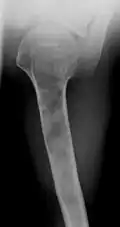

X-ray showing enchondromas localized in the humerus of a 37-year-old patient affected with Ollier disease -